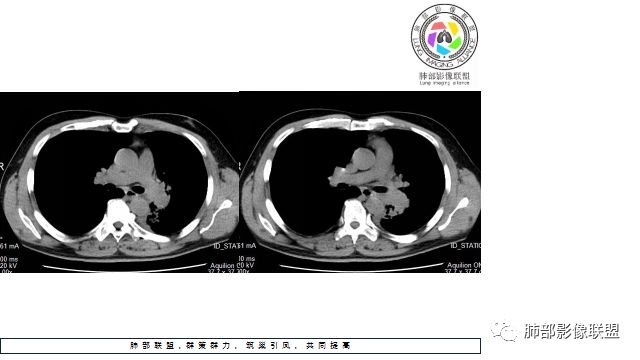

1.左下肺门区巨大肿块,支气管显示不清,轻度阻塞性炎症,没有明显肺不张,提示管腔受压狭窄可能性大于堵塞,这较少见于鳞癌。

3.病灶内密度均匀,轻到中度均匀强化,大病灶未见明显液化坏死区及空洞,不符合鳞癌而符合小细胞肺癌特点。

4.病灶内有肺动脉走形,血管局部受压,未见破坏,病灶乏血供,呈血管包埋或血管造影征;侵袭性力强及破坏力弱、血管漂浮都符合SCLC,所以鳞癌的可能性也不大。

5.左肺门块影或淋巴结肿大,竭力挤兑肺门血管结构,呈冰冻肺门;有时候SCLC可以单独呈现冰冻肺门,而没有没有冰冻纵隔。

7.须特别注意的是,肺门区的融合块影,不排除它可能仅仅为转移淋巴结。